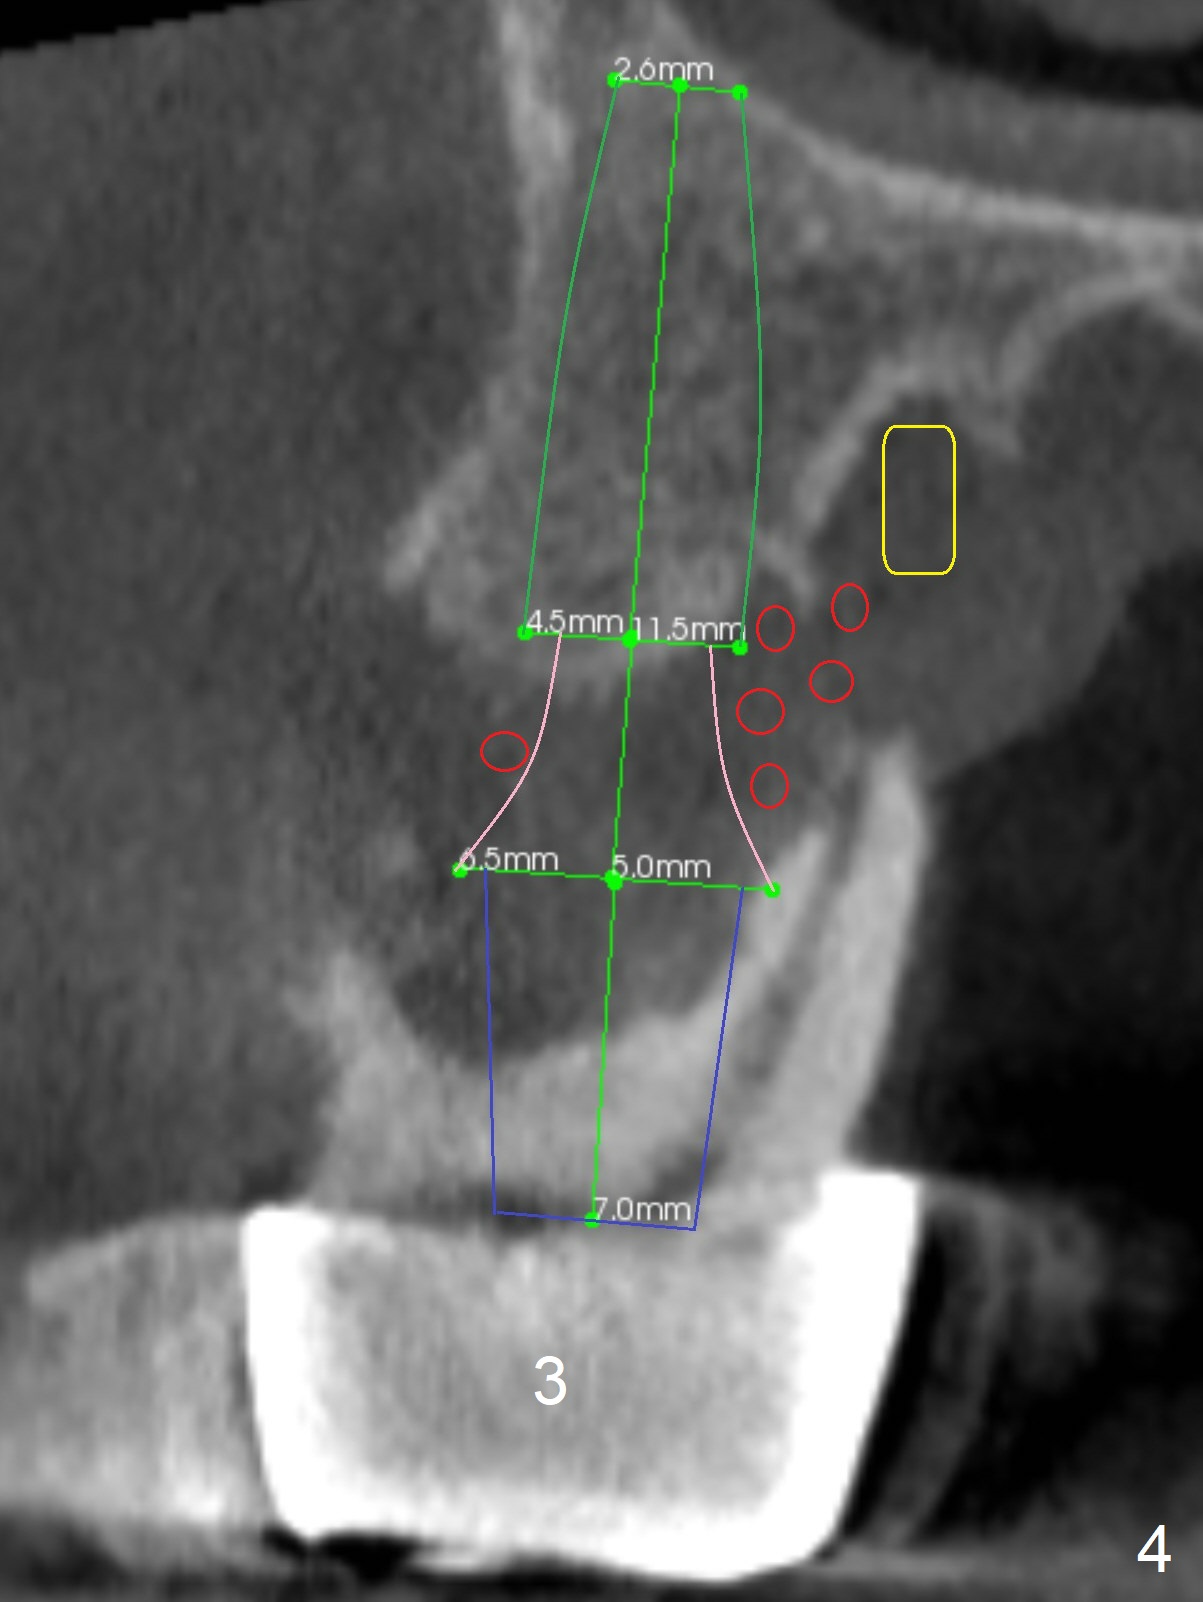

Extract #2 or remove #3-5 FPD first whichever is looser. Use the other as reference guide. Place Osteogen plug in the palatal socket of #2 ad 3 (Fig.3,4 yellow box) and allograft around the implants (red circles).